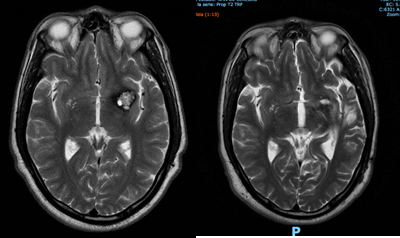

Ej. 1. Paciente con cavernoma incidental subinsular izquierdo en paciente joven que, en IRM de control, demostró crecimiento de la lesión y se decidió cirugía con buena evolución.